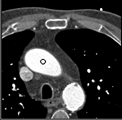

Samples for ascending aorta detection (black circle):

Cluster of candidate points in the ascending aorta.